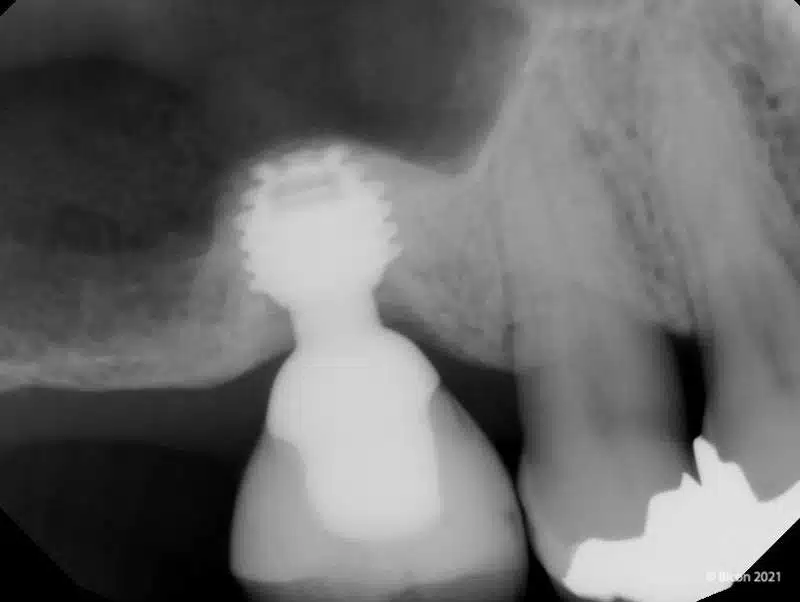

Uno studio retrospettivo pubblicato su Materials (2020) ha valutato l’efficacia di impianti corti e ultra-corti con connessione locking-taper, inseriti in associazione a rialzo del seno mascellare per via crestale (internal sinus lift).

- Survival rate implantare: 96,08%

- Aumento dell’altezza ossea: da 5,2 mm a 7,59 mm

- Guadagno osseo medio intra-sinusale: +3,17 mm

- Perdita ossea crestale media: 0,29 mm

I livelli ossei peri-implantari si sono mantenuti stabili nel tempo, nonostante condizioni iniziali di ridotta disponibilità ossea.